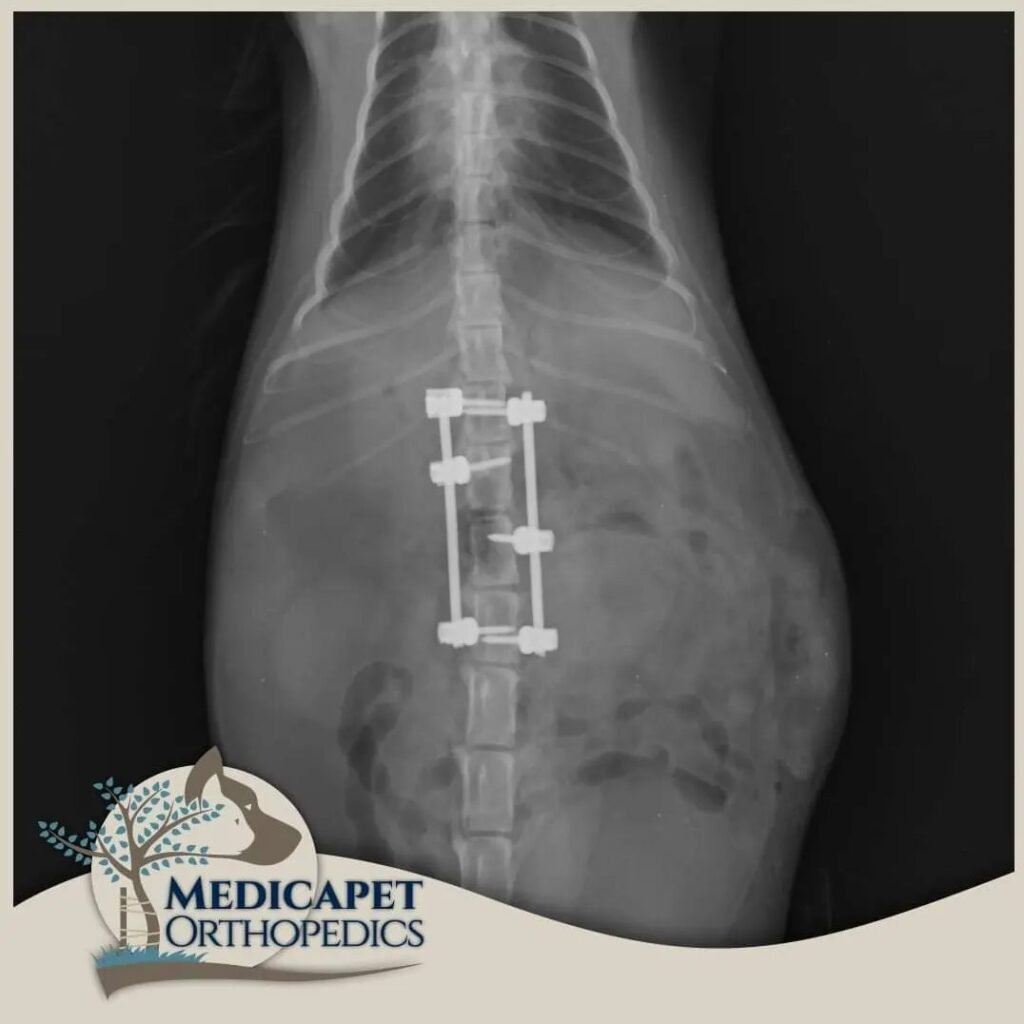

omurga cerrahisi

omurga kırıkları, disk fıtığı gibi olgularda acil müdahale başarı şansını yüksetir.

zaman geçtikçe kalıcı felç olasılığı artar.

zaman geçirmeden bize ulaşın

Kliniğimizde karşımıza çıkan sinir sistemi hasarlı hastaların pek çoğu bu hasarı bazı kazalar

sonucunda almış olarak geliyorlar. Trafik kazaları, yüksekten düşmeler, insan saldırısı, başka bir

hayvanın saldırısı gibi olayların sonucunda özellikle omurgada kırıklar, kırık bulunmayan omurga

travmaları, kafatası hasarları, kol – bacak ve kalça kırıklarına bağlı geçici ya da kalıcı felç durumları

gibi durumlar en sık tedavi ve opere ettiklerimizin başında geliyor. Öte yandan bazı ırkların genetik

yatkınlıkları da omurga problemlerine yol açabiliyor.